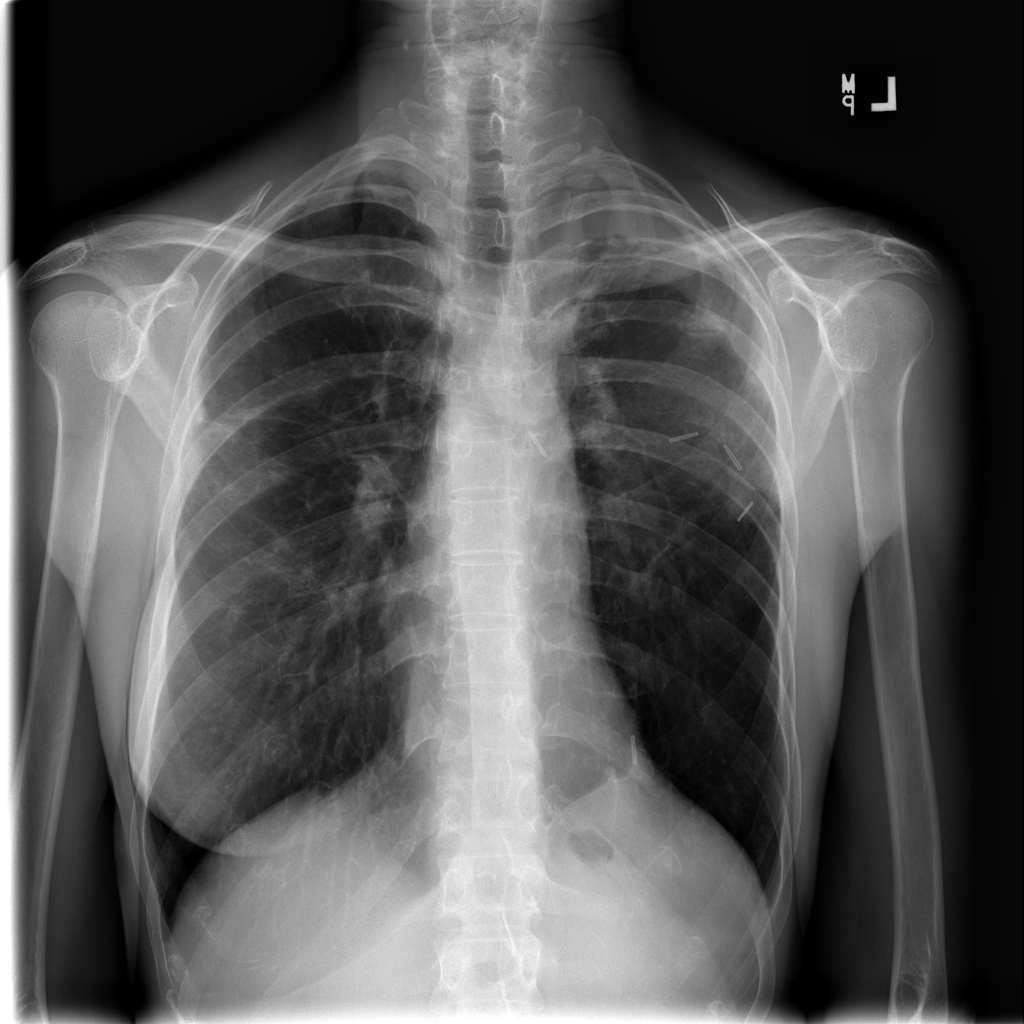

PAT-E066 · IMG-010Fibrosis

PAT-E066 · IMG-010

PA